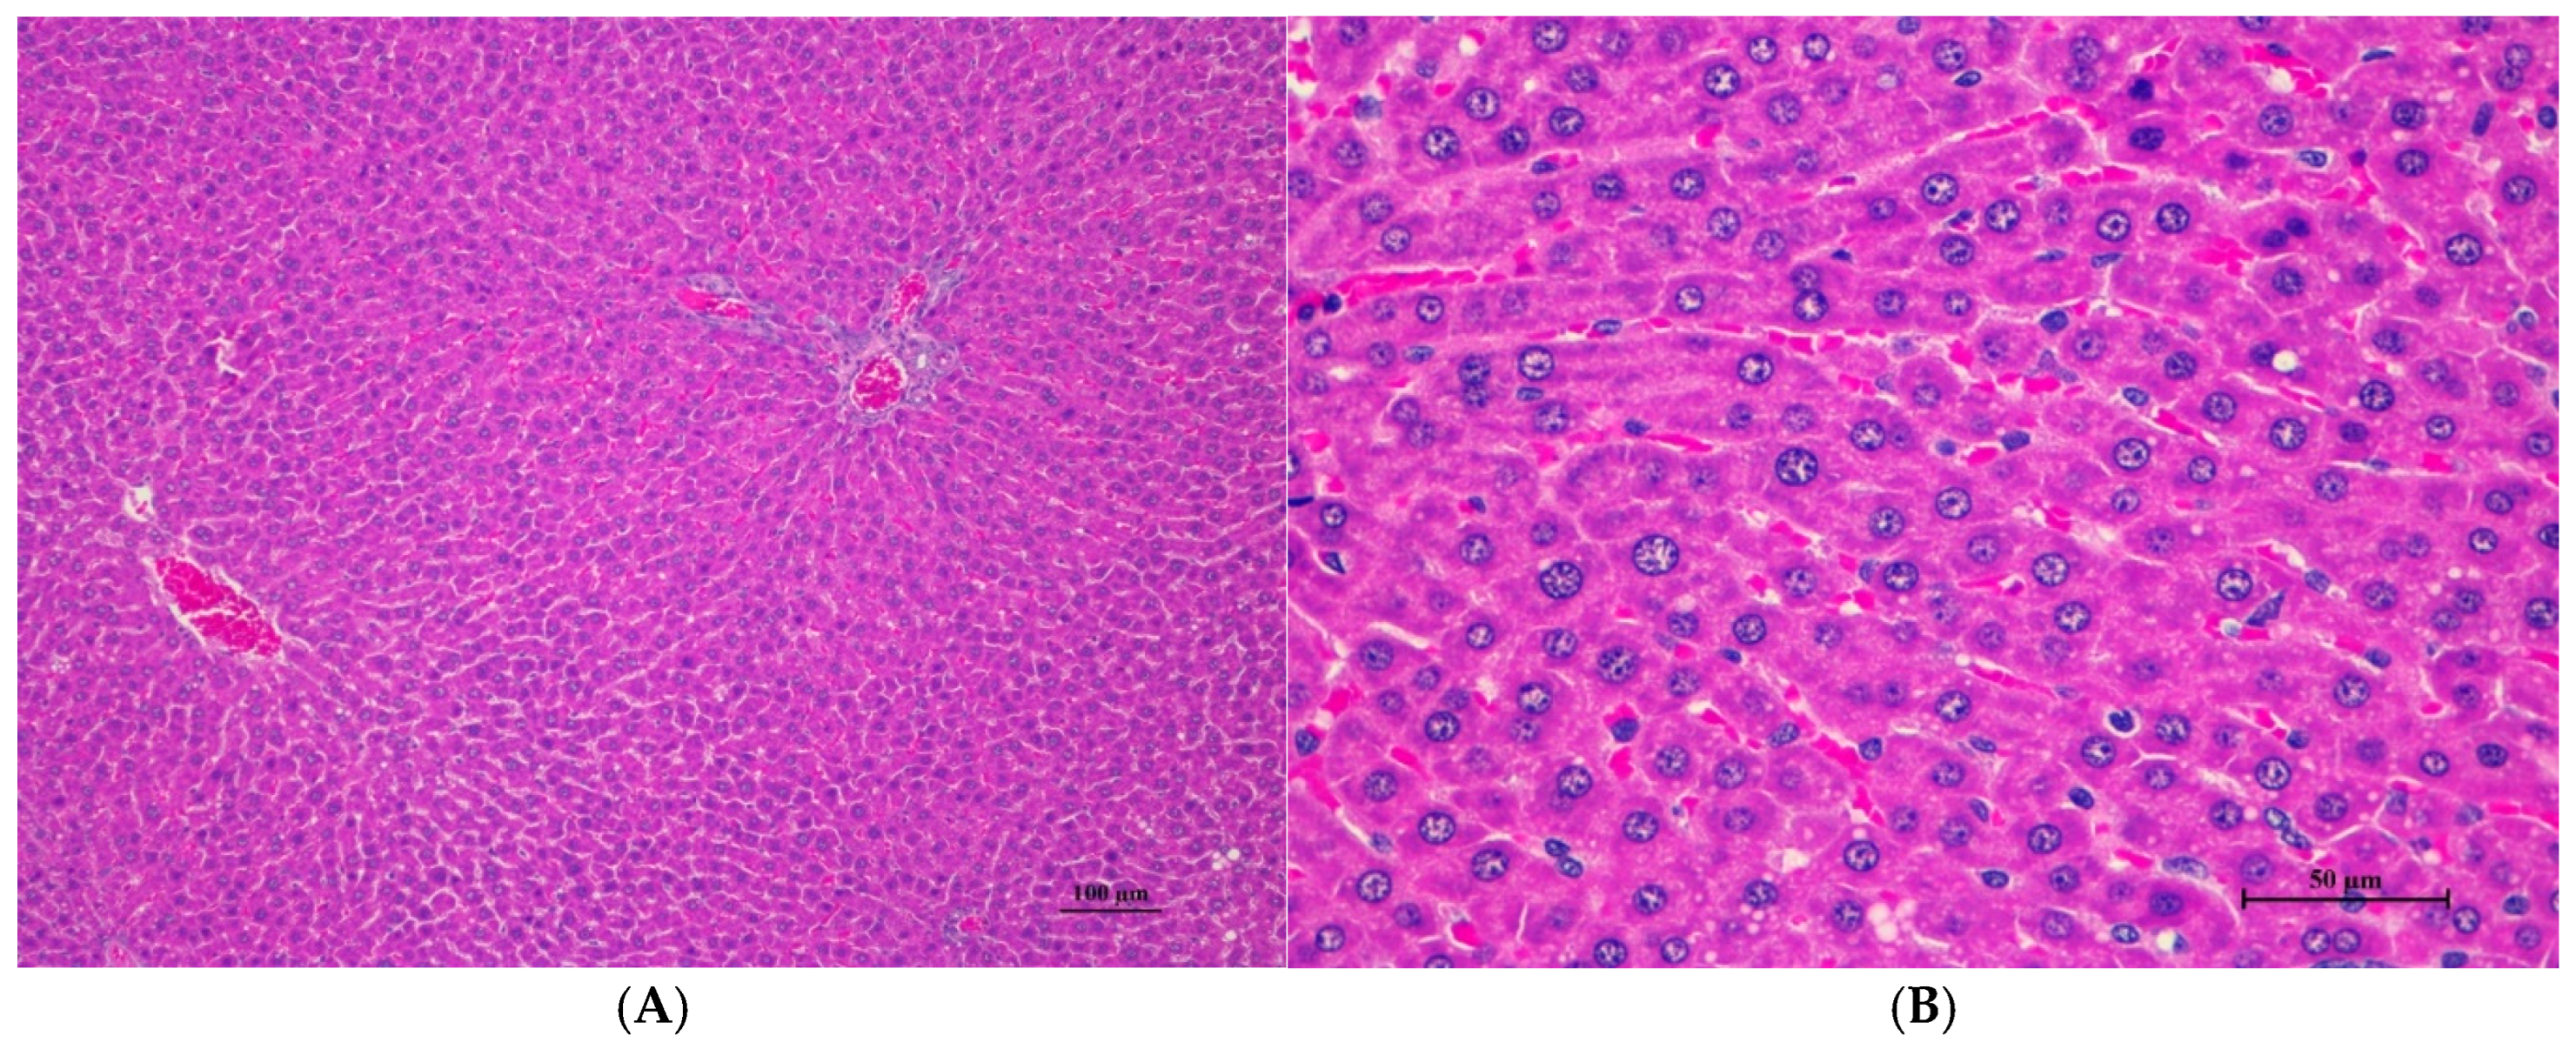

Figure 1.

Histopathological examination of rat liver tissue in acute toxicity from a single oral dose of CDF demonstrated minimal and non-pathological changes. (A) The hepatic parenchyma showed a normal central vein, hepatic portal triad, and hepatic cord (100×, H&E). (B) High magnification shows polygonal hepatocytes with central nuclei. Very mild cytoplasmic swelling and fine vacuolation were observed in some hepatocytes (400×, H&E).

Histopathological analysis revealed generally unremarkable findings in the liver, kidney, heart, and spleen, with only minor, scattered hepatocellular swelling and vacuolation in the liver, mild renal tubular degeneration in limited kidney areas, and focal myocardial vacuolation and lymphoid aggregation in the heart. Conversely, the lung exhibited significant pathological changes, characterized by alveolar septal thickening due to severe interstitial infiltration of lymphocytes and other mononuclear cells, nodular lymphoid aggregations, alveolar septal engorgement and hyperemia, alveolar edema, and multifocal mild alveolar hemorrhage, suggesting a potential site of inflammatory response.

Histopathological changes in the liver of male rats including hepatic vacuolation and hepatic degeneration were found in the control group and 175AM, 550AM, and 550AF groups. Abnormalities were found in the cytoplasm of liver cells, to a mild degree and diffuse in some areas of the liver, and portal tracts were normal. These findings were minimal and considered non-significant lesions. Furthermore, biochemical values were minimally changed and remained within the normal range, which led to the interpretation of the organ being normal.